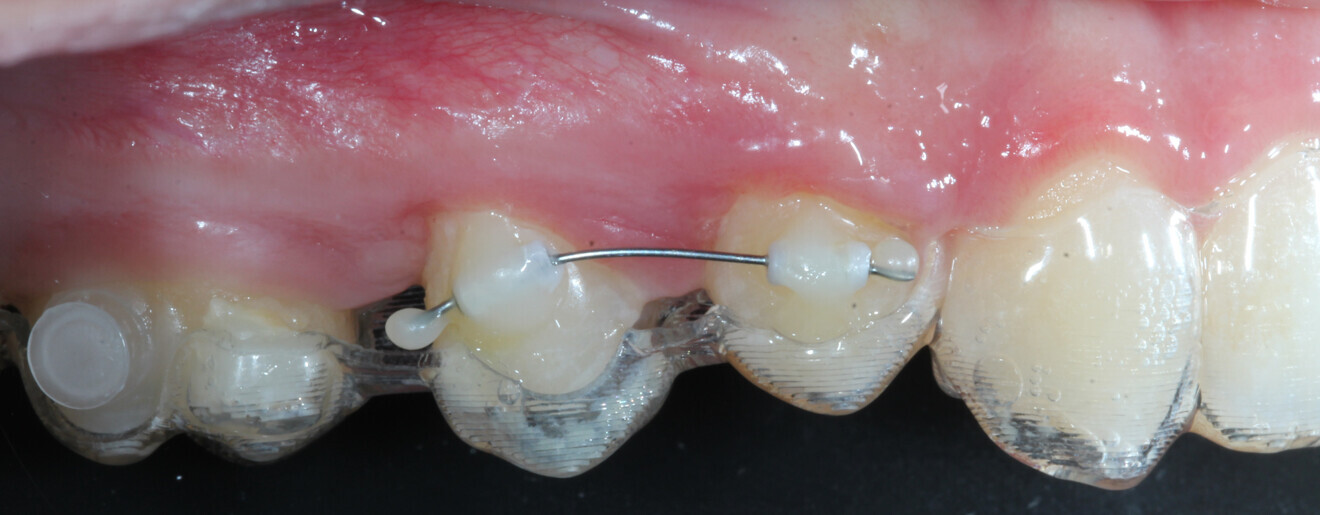

At the end of the first stage of aligner treatment (Figs. 20–24), the auxiliary phase began with the bonding of two MTAs on the maxillary right premolars. A 0.016-in Australian archwire, shaped into a cantilever configuration, was then inserted into the MTAs, and a cutout was created on the final aligner. To prevent rotation, the archwire was cinched distal to tooth #15 and the cinch covered with composite.

At the same time, the impacted canine was exposed by laser, a button was bonded on to it and the cantilever was connected to the button using an elastomeric thread. The final aligner was used for space maintenance while the cantilever was reactivated until the canine had erupted (Figs. 25–27). After complete eruption, further MTAs were bonded on the canine and on the lateral incisor, and a 0.014 in. NiTi archwire was used to finalise the eruption (Figs. 28–30). Only at the end of the forced eruption phase did the further aligner stage take place, aimed at achieving an ideal Class I relationship on the right by maxillary right mesialisation using Class III elastics and 27 maxillary aligners and 13 mandibular aligners (Figs. 31–33).